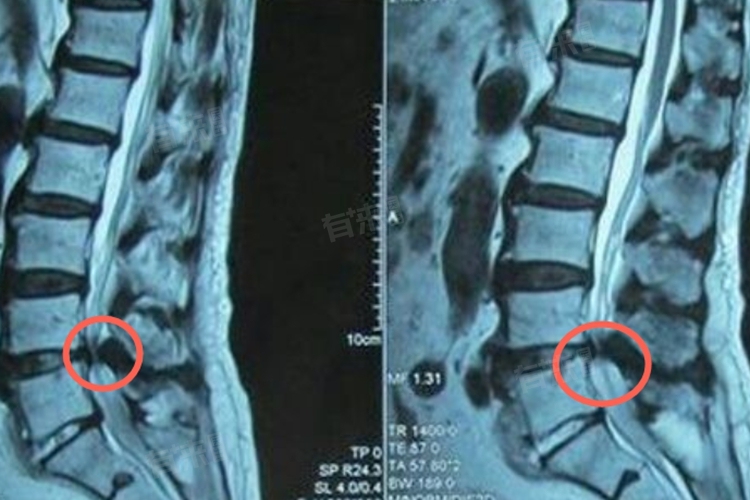

2、椎间盘突出:当腰椎间盘发生退行性改变或受到外伤时,可能会突出并压迫神经根或脊髓,这一变化是腰椎管狭窄加重的重要标志,患者可能会开始感受到腰痛、下肢麻木或无力等症状,尤其在行走或长时间站立后更为明显。